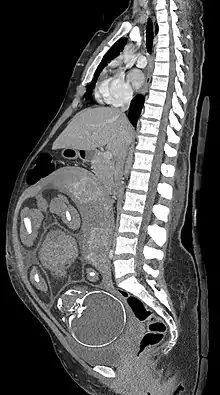

Median plane CT scan of a pregnant woman. The fetus (exposed in the coronal plane) is 37 weeks of gestational age.